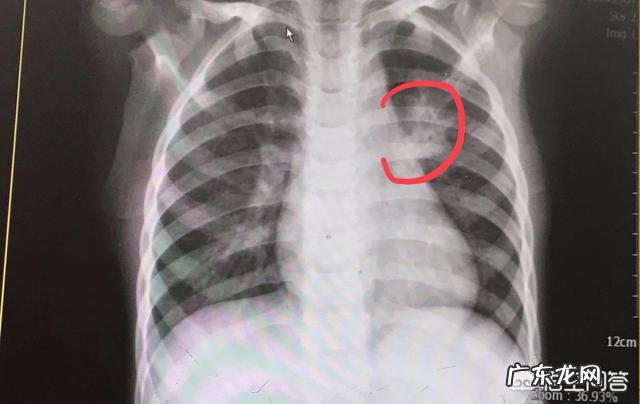

1、咳嗽有痰 , 往往为细菌性支气管炎 , 肺炎导致咳嗽 , 往往有较多分泌物 。

【小孩咳得厉害怎么办?】2、鼻炎鼻窦炎导致鼻涕倒流的咳嗽 , 往往有痰 , 鼻炎往往为清水样